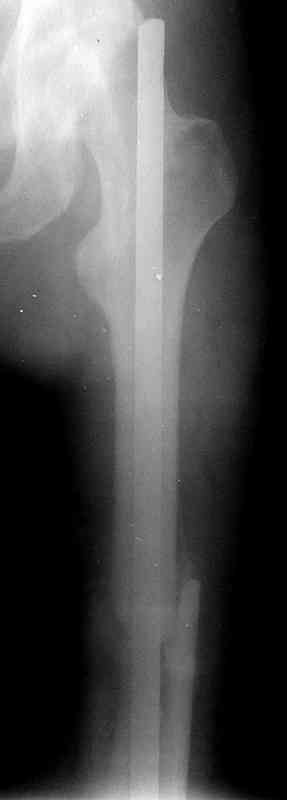

Фиксаторы удалены через 12 месяцев после операции, выполненной по поводу замедленной консолидации перелома бедра с его укорочением.

На финальных снимках видно - сращение прям таки железное. Если Вы не устали отвечать, осмелюсь задать еще вопрос - что-то принимал пациент в целях ускорения сроста (кальций, режим питания). Интересны также вопросы восстановления функций конечности - в какой период были рекомендованы группы упражнений для восстановления основных групп мышц?